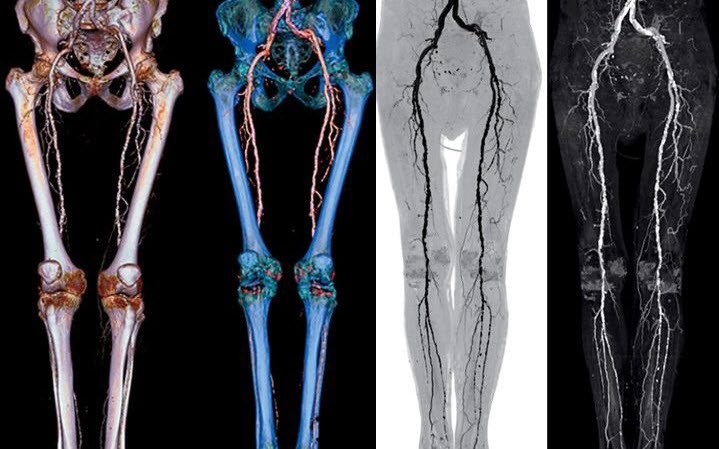

- Ультразвуковая диагностика (дуплексное сканирование: обычная методика в сочетании с допплеровским исследованием). Во время её проведения измеряется кровоток в патологически изменённых сосудах, при наличии заболевания он значительно снижен.

- Компьютерная томография с применением контраста – позволяет выявить процент окклюзии по отношению к здоровой части артерии и протяжённость патологически изменённого участка. Используется не только для диагностики, но и для проведения обследования перед оперативным вмешательством.

- Контрастная ангиография. Проводится, если запланирована инструментальная терапия с хирургическим вмешательством.

- Магниторезонансная ангиография – менее предпочтительная альтернатива вышеописанным методам.